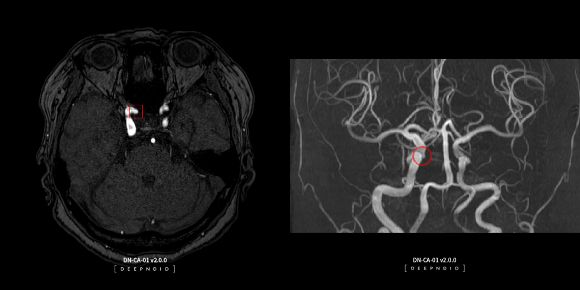

의사의 AI설루션 개발 지원, AI영상진단 생태계 주도 '딥노이드' 딥노이드는 AI설루션 개발에서부터 배포, 활용 등의 AI영상진단 전 과정에서 생태계를 구축하고 있다.

직접 AI설루션을 개발하는 파이프라인 방식뿐만 아니라 의료인이 AI설루션을 개발할 수 있도록 돕는 플랫폼 방식의 '투트랙' 사업모델을 운영하고 있다. 이 중 플랫폼 방식은 회사 내부 개발비용을 줄일 수 있는 장점이 있다. 현장의 수요(니즈)를 반영해 동시에 여러 설루션 개발을 추진할 수 있어 국내 AI영상진단기업 중 식약처로부터 가장 많은 설루션 품목허가를 받았다.

뇌혈관, 폐, 척추, 흉부, 유방 등 다양한 질환영역에서 18종의 AI설루션이 출시됐는데 경희의료원, 부산대학교병원 등 주요 대학병원은 물론 심평원에도 AI설루션을 공급하고 있다. 특히 심평원은 AI영상 저장 및 전송시스템 구축에 딥노이드의 AI영상 판독지원 설루션 딥팩스를 활용 중이다.